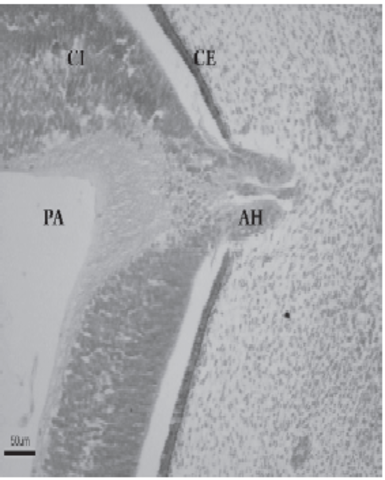

Desarrollo del cristalino

La placoda cristaliniana se invagina, hasta que un día más tarde se desprende de la superficie ectodérmica, formando la vesícula cristaliniana. Inicialmente ésta presenta una cavidad en su interior. Este fenómeno coincide con la aparición del cuerpo vítreo primario, entre la vesícula y la cúpula óptica Las fibras de la pared profunda de la vesícula cristaliniana se diferencian para formar las fibras primarias del cristalino. De esta forma, se va obliterando lacavidad de la vesícula cristaliniana

La vesícula del cristalino recibe irrigación de la arteria hialoidea, que también irriga a la retina en desarrollo. Cuando el cristalino madura en la vida fetal, la porción de la arteria hialoidea que cruza el cuerpo vítreo degenera, dando lugar en el adulto al ligamento de CloquetStilling, que se dispone desde la cara posterior del cristalino hasta la papila. La porción proximal de la arteria hialoidease convierte en la arteria central de la retina.